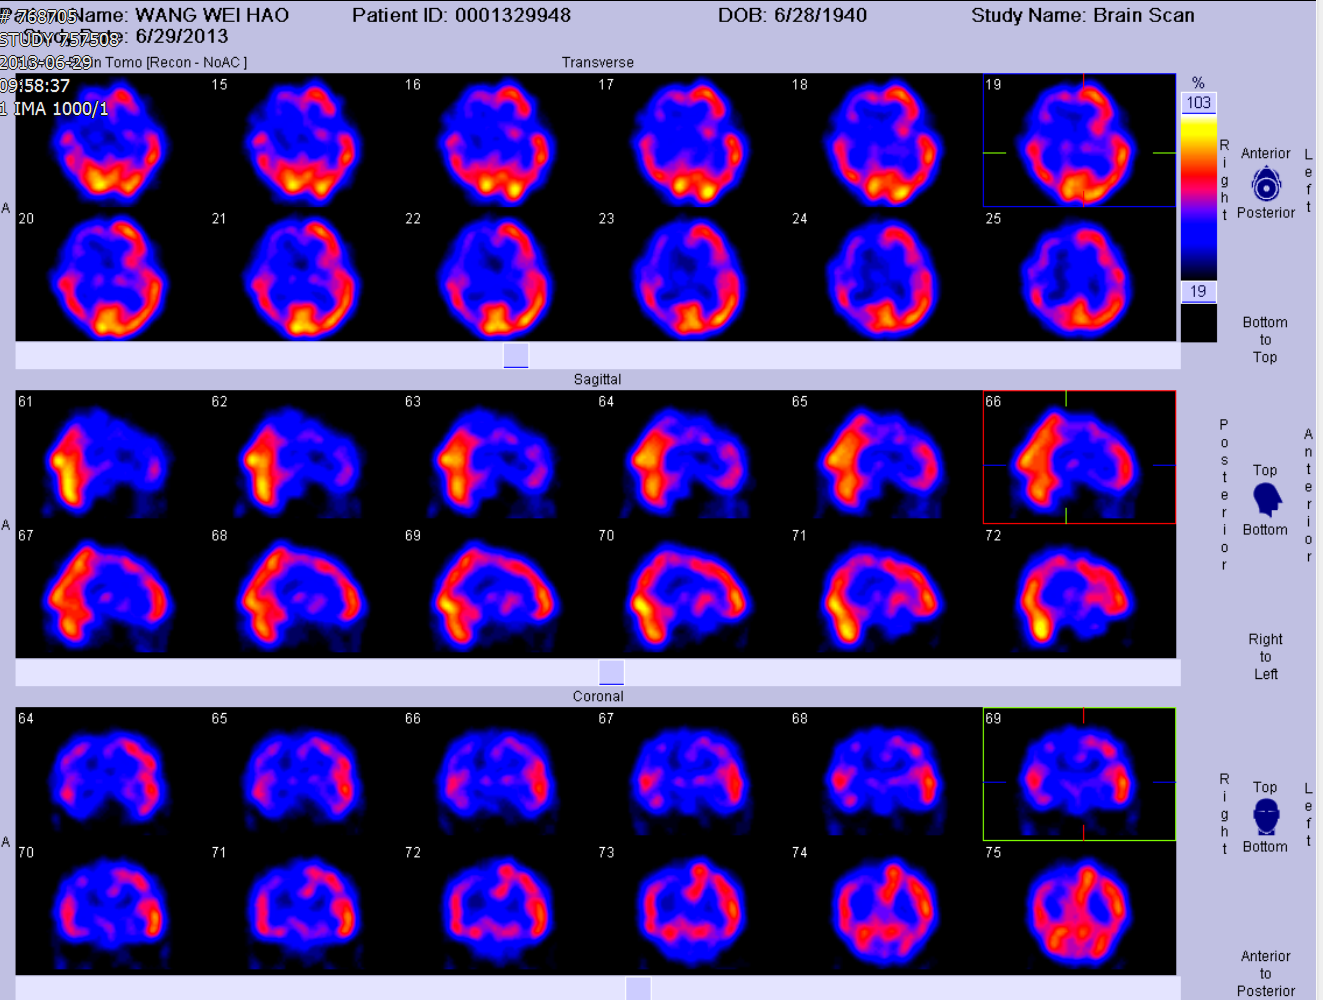

术后头颅ECT显示右侧血流灌注明显增加

术前